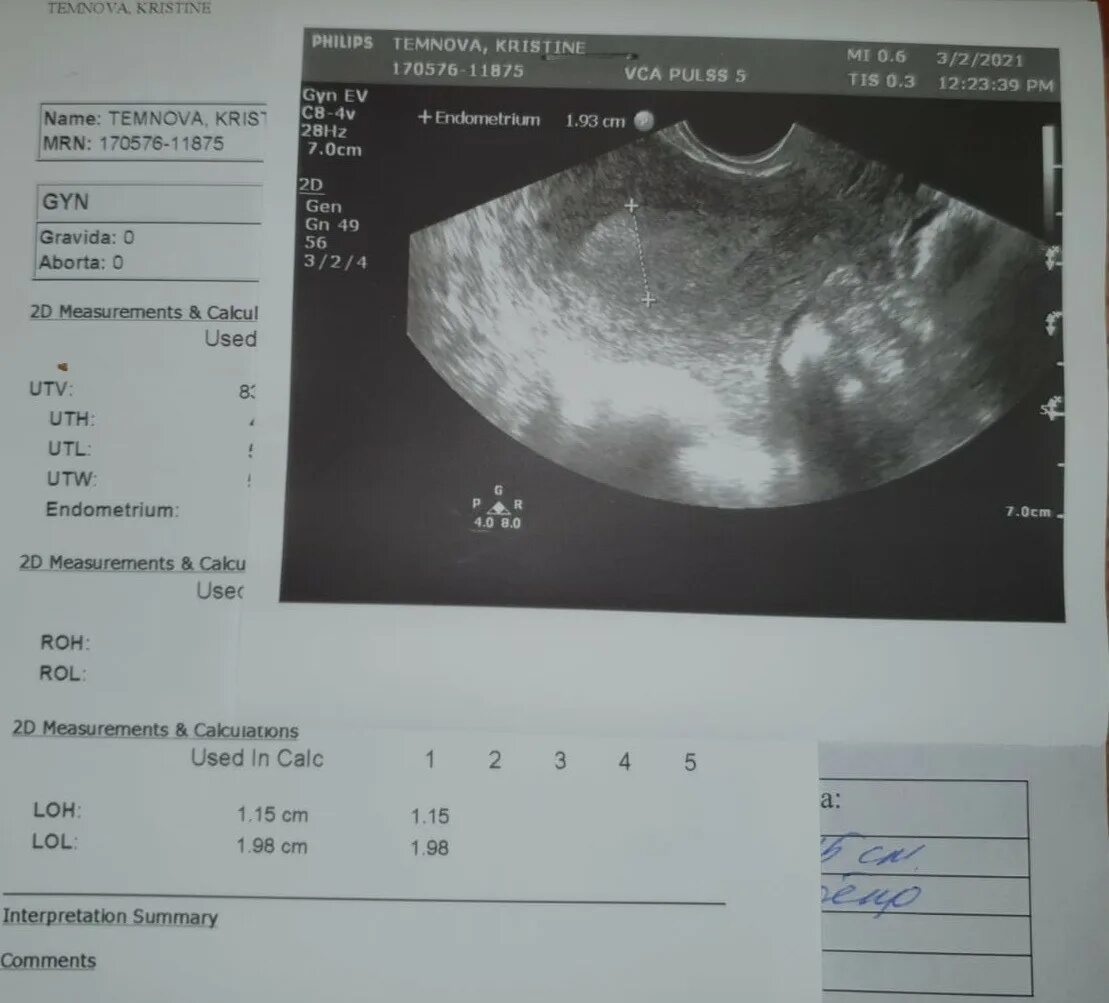

Белое пятно на узи